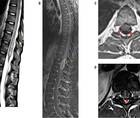

Case Report: Longitudinally Extensive Transverse Myelitis

Ylec Mariana Cardenas, MD; Lakshmi Leishangthem, MDYlec Mariana Cardenas, MD; Lakshmi Leishangthem, MD - Stroke